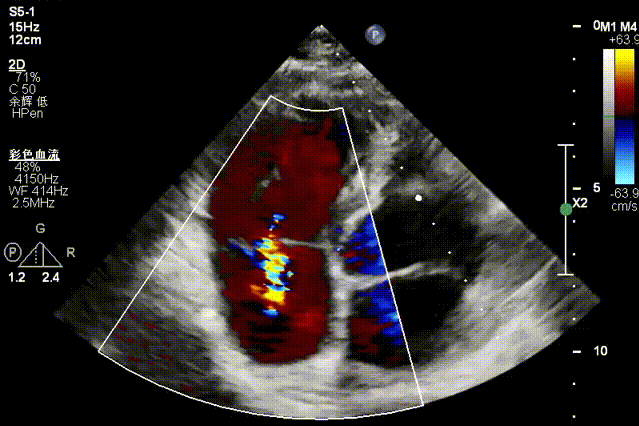

Mitral Valve Repair Stage: Via the transfemoral venous approach, a 4.0 cm atrial septal puncture was performed, and one mitral valve clip was selected. The unique feature of wide-angle deployment effectively resolved the issue of excessive leaflet tension during valve clip closure. Under the precise guidance of ultrasound, one clip was successfully implanted at the site of the widest regurgitation in the A2-P2 segment of the mitral valve. Immediate postoperative TEE assessment showed that mitral regurgitation was reduced to trivial (1+), the mean transvalvular pressure gradient was only 3 mmHg, and pulmonary venous retrograde flow was significantly improved.

Regurgitation Essentially Eliminated at 25° Closure

Trivial Residual Regurgitation Post Deployment

Stable Tissue Bridge

Transvalvular Pressure Gradient of 3 mmHg